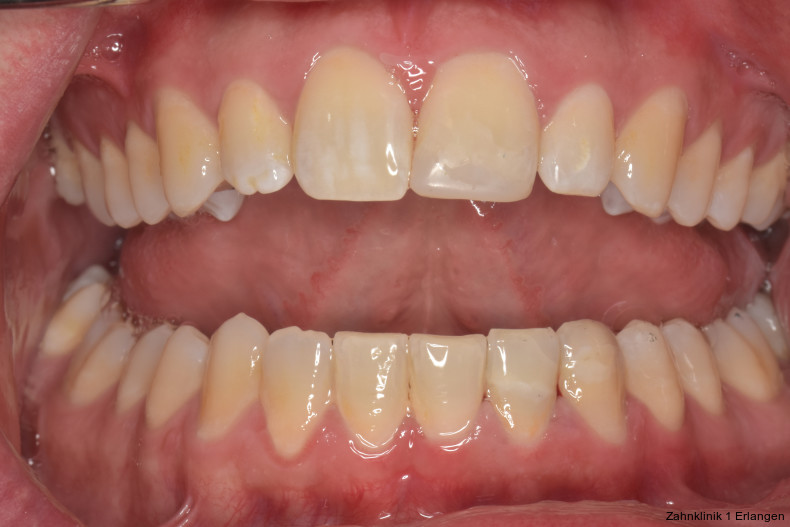

Das dentale Trauma stellt Zahnärztinnen und Zahnärzte in der Praxis immer wieder vor mehr oder weniger große Herausforderungen. Dies liegt zum einen daran, dass die Erst- und Weiterversorgung in den meisten Praxen nicht zur Routinebehandlung gehört und eher selten durchgeführt wird. Zum anderen ist dies auch dadurch begründet, dass dentale Traumata eine große Bandbreite an Komplexität aufweisen.

Da verschiedene Gewebe, neben den Weichgeweben also Zahnhartsubstanzen, Endodont, Parodont sowie knöcherne Strukturen, je nach Art und Schweregrad der Verletzung in unterschiedlichsten Kombinationen betroffen sein können, reicht die erforderliche Therapie von einfach bis hochkomplex.

Während die Erstversorgung relativ einfachen Grundprinzipien folgt, sind bei der weiteren Behandlungsplanung oft verschiedene Therapieoptionen interdisziplinär abzustimmen. Insbesondere bei jungen Patienten gilt es, Komplikationen zu antizipieren und wenn möglich zu vermeiden oder frühzeitig zu erkennen, um betroffene Zähne längstmöglich zu erhalten. Nicht selten verursachen die Folgen der Verletzungen nach schweren Zahntraumata noch jahrelang Behandlungsbedarf.